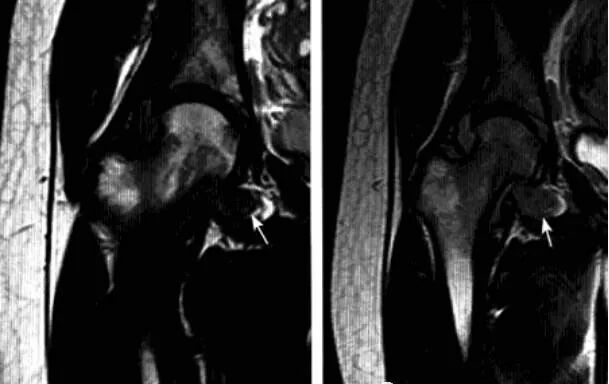

髋关节色素沉着绒毛结节性滑膜炎

一种侵及关节、腱鞘、滑囊或肌腱组织的良性增生伴色素沉着性病变。一般单关节发病,*常累及膝关节,其次是髋关节、踝关节、肩关节、肘关节。

病理:表面凹凸不平,有绒毛状滑膜皱襞覆盖,累及关节囊及周围软组织内血管和神经结构。

临床表现:以20-40岁青年女性多见,多有髋部外伤史,早期无特征,进展缓慢。

影像诊断:早期诊断缺特异性,晚期出现典型骨质破坏。MRI检查具较强特异性及定性诊断作用。